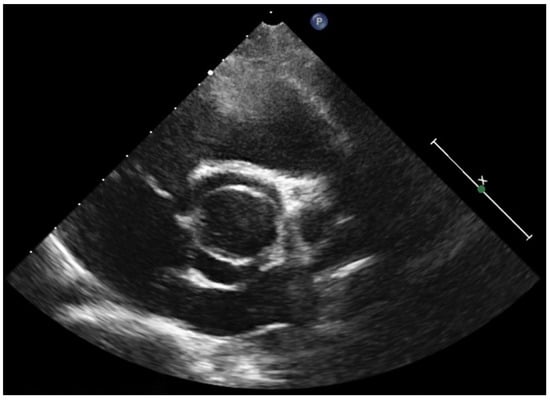

5. Diagnostic Imaging